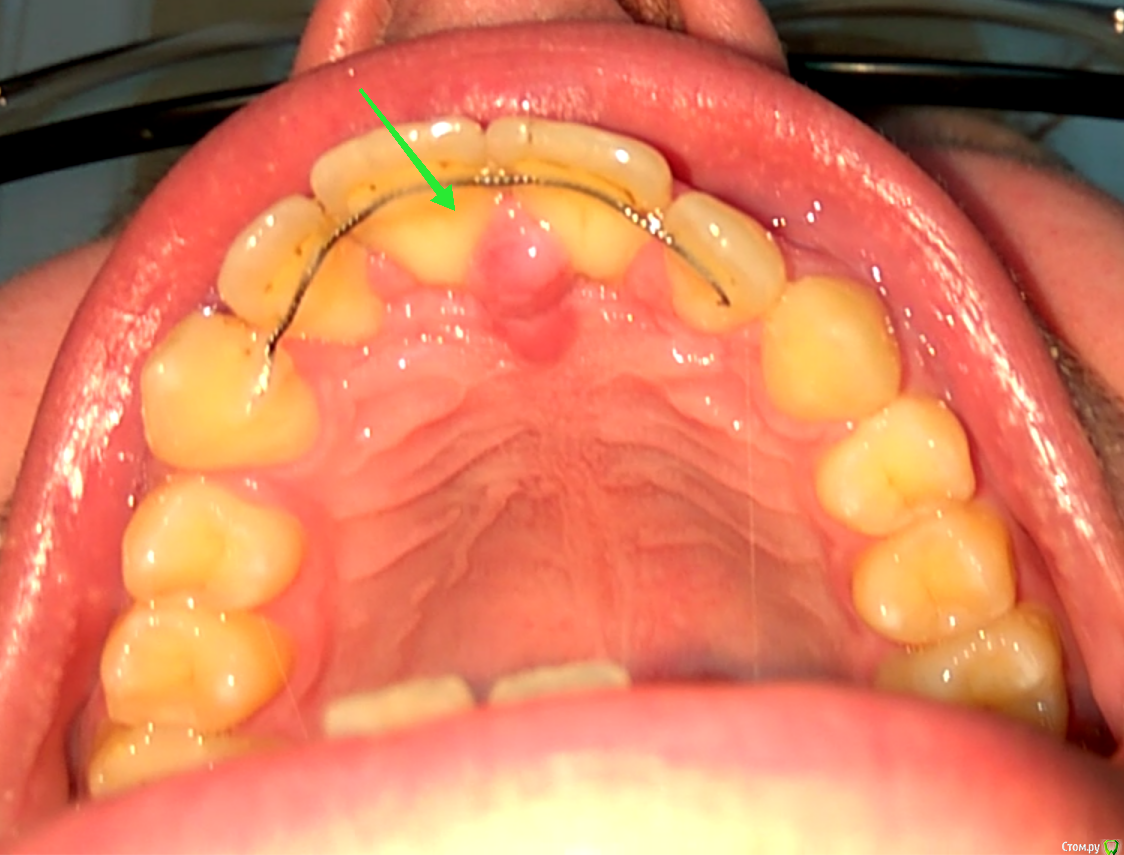

Anthonyc Опубликовано 10 марта, 2018 Поделиться Опубликовано 10 марта, 2018 (изменено) Здравствуйте! Меньше недели назад болел гриппом, пил лекарства...и заметил воспаление на верхнем небе по середине между двумя передними зубами. У меня раньше такое было, потом само проходило.Воспаление не проходит уже четвертый день, в самом начале даже жевать мешало, сейчас шишка стала меньше, утром , как только проснусь этот "шарик" увеличен в размерах, а днем становится меньше, вчера даже кровь вышла с десен в том месте. Не болит, но дискомфорт на психологическом уровне дает.Что это может быть? После гриппа я до конца еще не восстановился, может ли это быть как-то связано? P.S. Около 10 лет назад мне ставили брэкеты (передние зубы были деформированы вперед , т.к в детстве сосал палец), и в этом самом месте хирург что-то вырезал, что именно я не помню и для чего. Изменено 10 марта, 2018 пользователем Anthonyc Ссылка на комментарий

Anthonyc Опубликовано 14 марта, 2018 Автор Поделиться Опубликовано 14 марта, 2018 (изменено) А что собираются удалять?Еще у хирурга не был, но стоматолог сказала что вот это. Не знаю права ли она. Изменено 14 марта, 2018 пользователем Anthonyc Ссылка на комментарий

red_butler Опубликовано 15 марта, 2018 Поделиться Опубликовано 15 марта, 2018 это анатомическое образование, удалять не надо. Сделайте Rg. Вы со своим ортодонтом обсуждали срок ношения ретейнера, не пора снимать? Ссылка на комментарий

Anthonyc Опубликовано 15 марта, 2018 Автор Поделиться Опубликовано 15 марта, 2018 (изменено) это анатомическое образование, удалять не надо. Сделайте Rg. Вы со своим ортодонтом обсуждали срок ношения ретейнера, не пора снимать?Я так понял он на всю жизнь О_0, я его ношу уже 8-ой год, может он и не нужен уже.Это анатомическое образование уже вторую неделю не проходит, а после сна увеличено в размерах и как шарик. Днем становится мягче и шарик проходит. Изменено 15 марта, 2018 пользователем Anthonyc Ссылка на комментарий

shishok Опубликовано 20 марта, 2018 Поделиться Опубликовано 20 марта, 2018 Ретейнер мешает нормальной гигиене.Как следствие-воспаление слизистой(в данном случае-воспаление резцового сосочка). Ссылка на комментарий